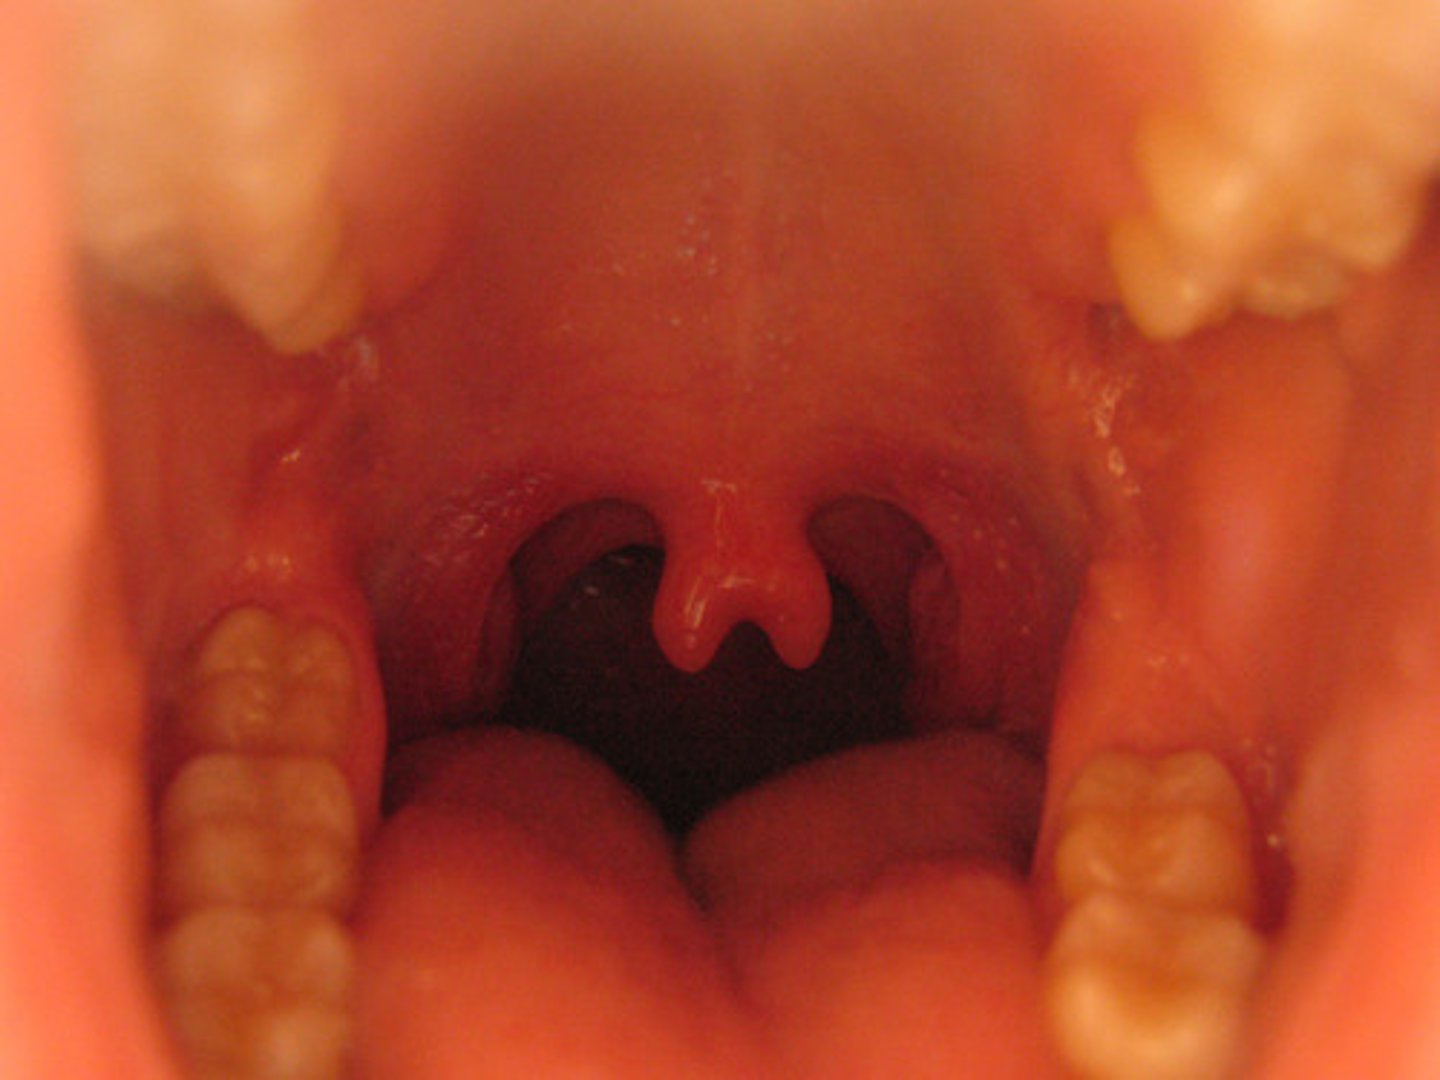

Describe physical variations of the oral cavity: bifid uvula

split uvula, looks like two